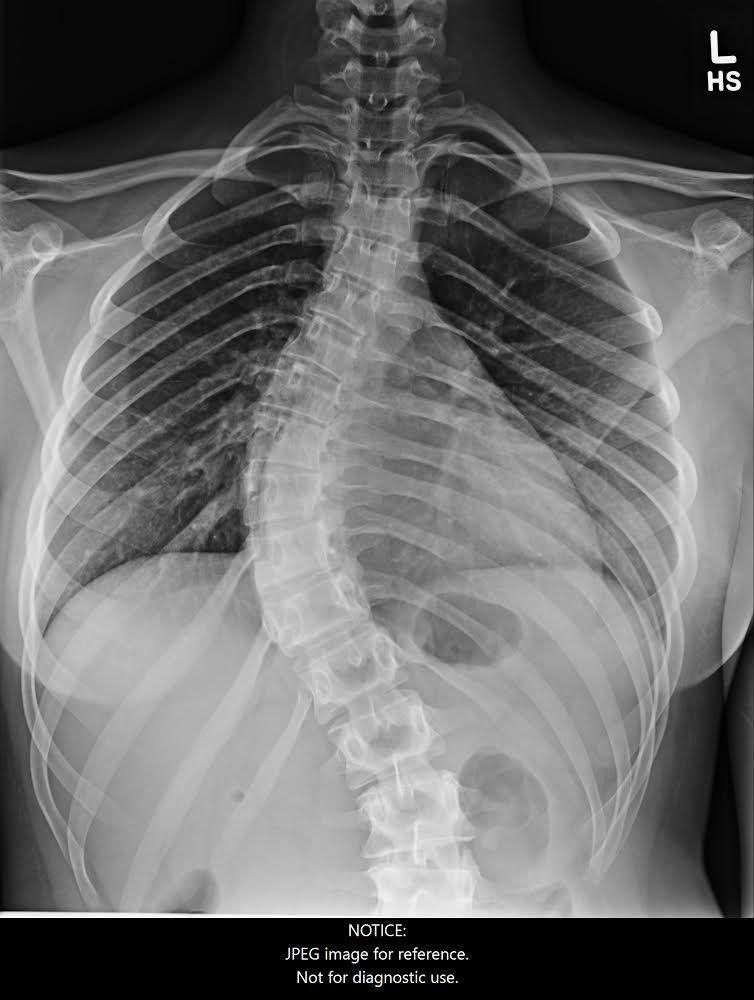

From medicine.utah.edu

Scoliosis Pathology Radiology U of U School of Medicine How Do You Sit With Scoliosis The weight should be spread out across your buttocks and thighs. In general, do’s include staying active while approaching certain activities with caution, and don’ts include. The problem impacts more than just the spine. The best way to sit if you have scoliosis is by trying to sit back into your chair while keeping your back straight. People with scoliosis. How Do You Sit With Scoliosis.